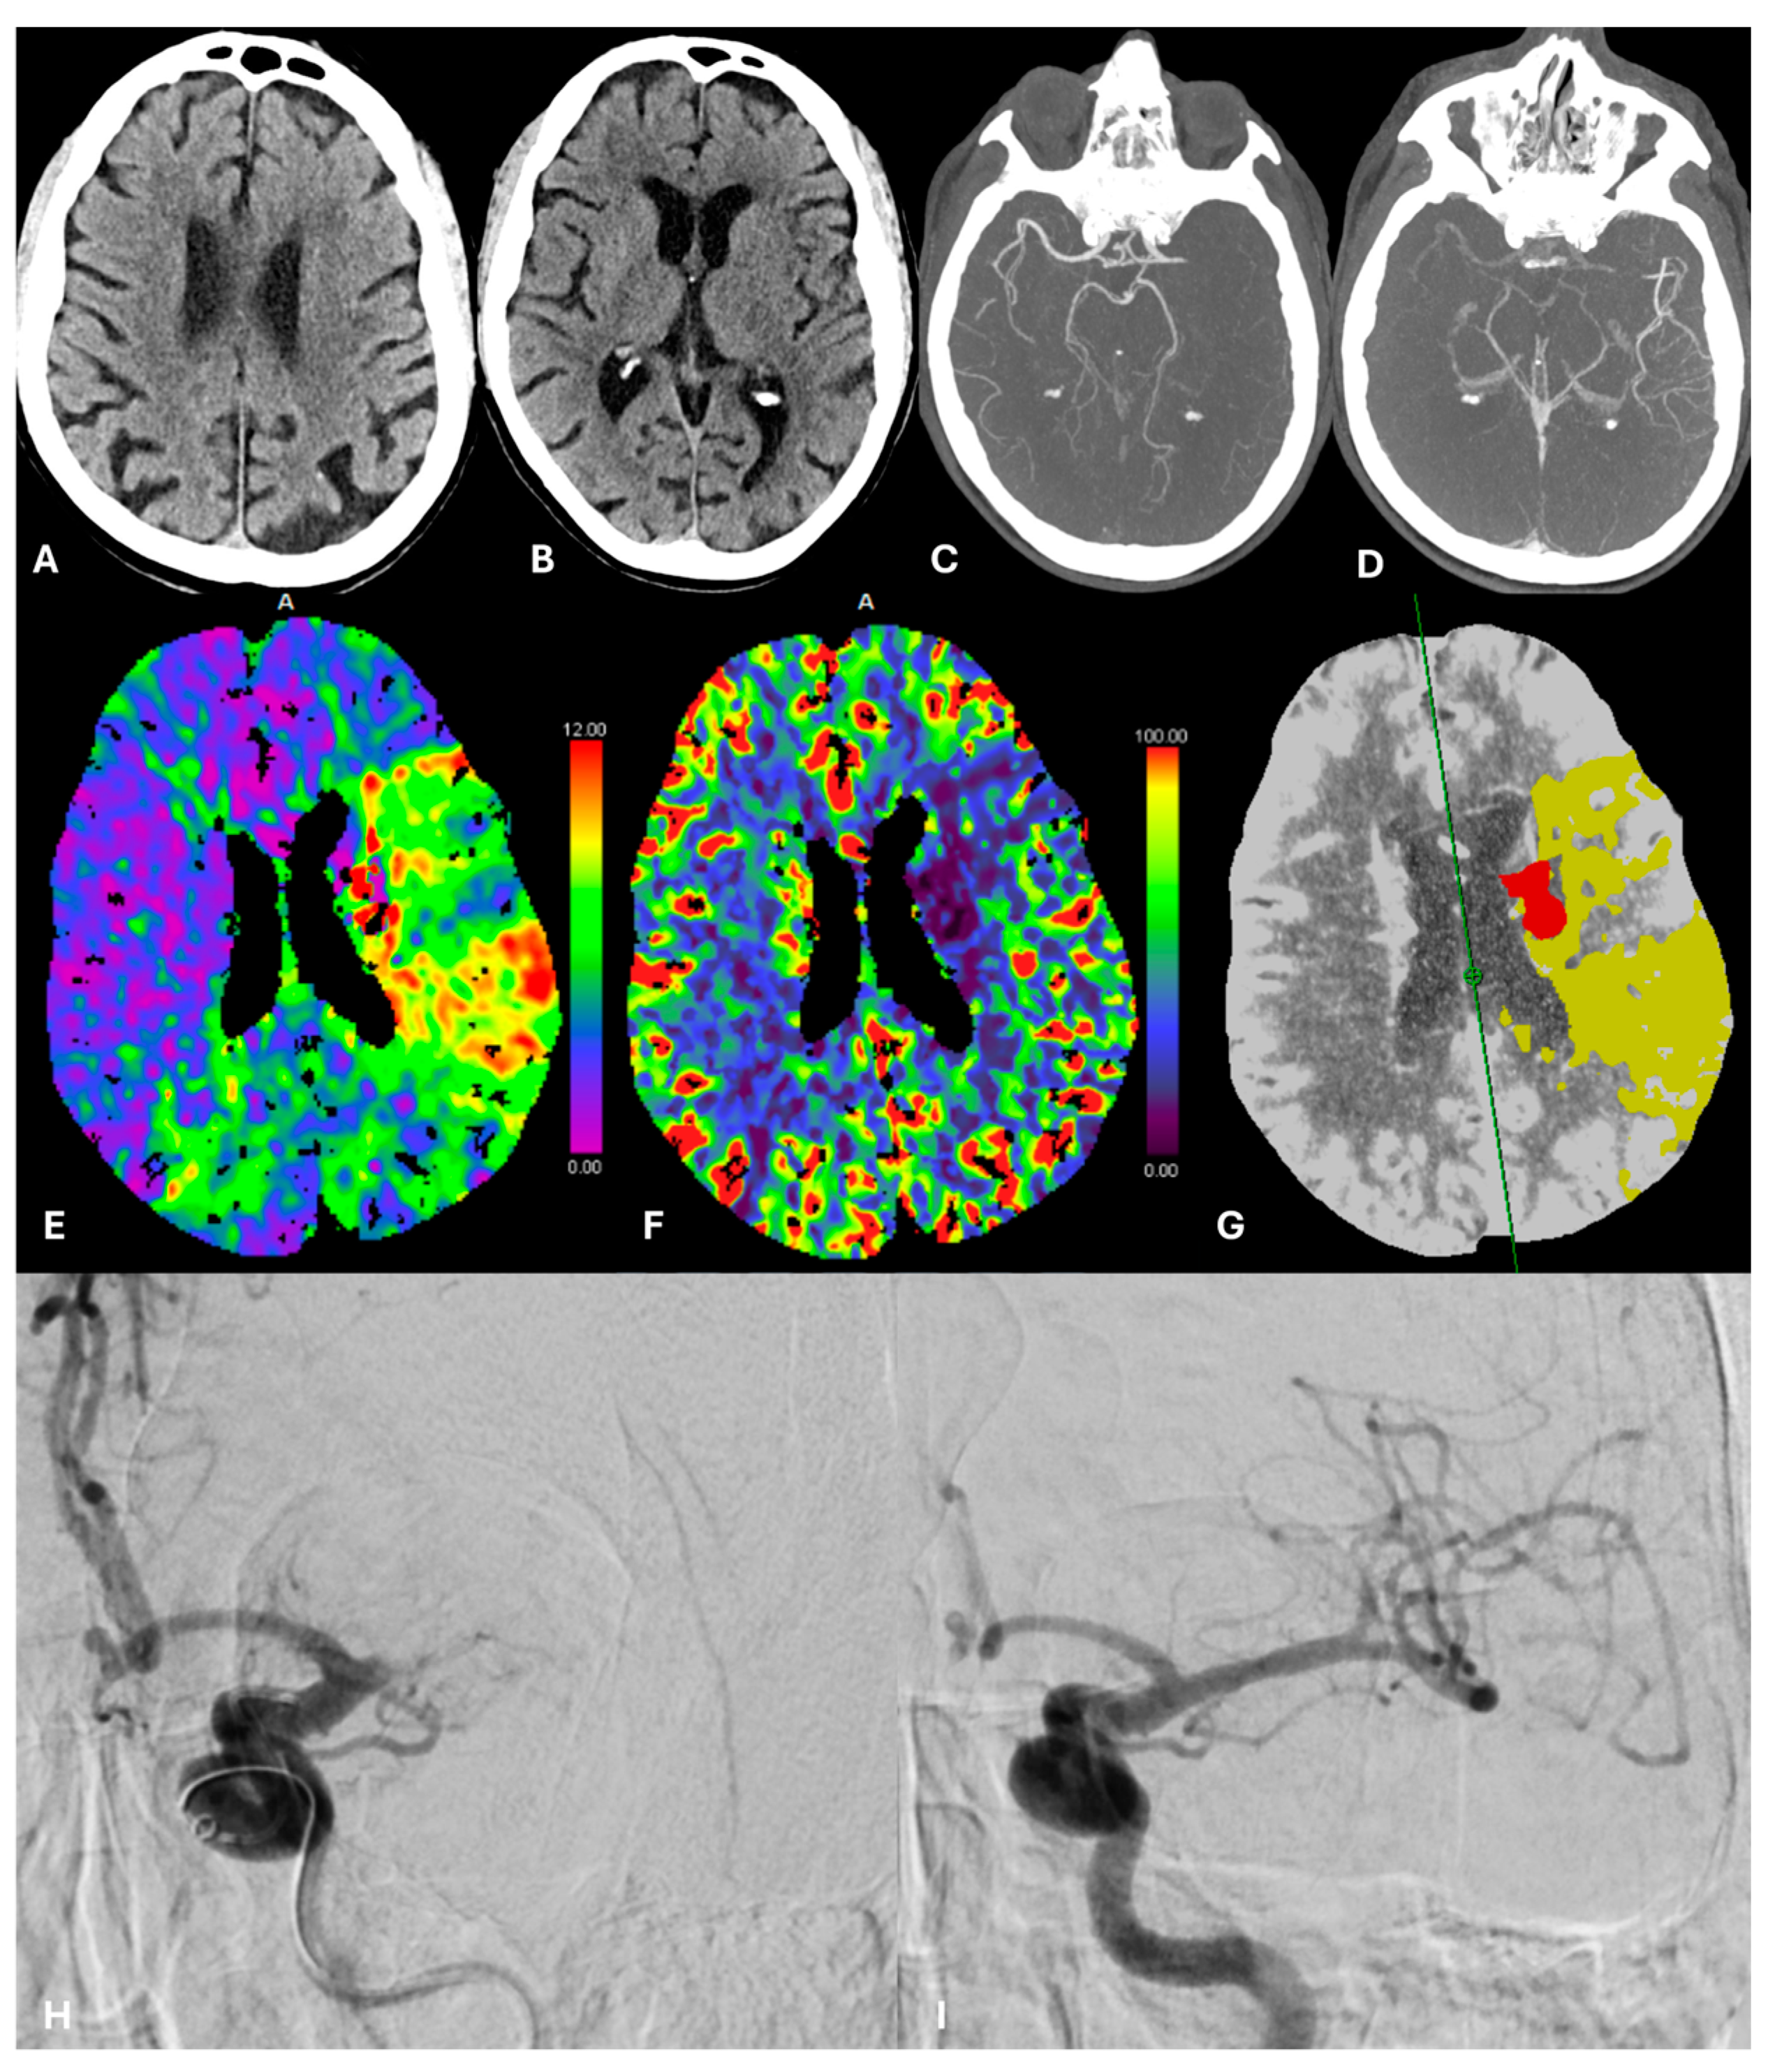

- Psychogios, M.N.; Maier, I.L.; Tsogkas, I.; Hesse, A.C.; Brehm, A.; Behme, D.; Schnieder, M.; Schregel, K.; Papageorgiou, I.; Liebeskind, D.S.; et al. One-stop management of 230 consecutive acute stroke patients: Report of procedural times and clinical outcome. J. Clin. Med. 2019, 8, E2185. [Google Scholar] [CrossRef] [PubMed]

- Mendez, B.; Requena, M.; Aires, A.; Martins, N.; Boned, S.; Rubiera, M.; Tomasello, A.; Coscojuela, P.; Muchada, M.; Rodríguez-Luna, D.; et al. Direct transfer to angio-suite to reduce workflow times and increase favorable clinical outcome. Stroke 2018, 49, 2723–2727. [Google Scholar] [CrossRef] [PubMed]

- Jadhav, A.P.; Kenmuir, C.L.; Aghaebrahim, A.; Limaye, K.; Wechsler, L.R.; Hammer, M.D.; Starr, M.T.; Molyneaux, B.J.; Rocha, M.; Guyette, F.X.; et al. Interfacility transfer directly to the neuroangiography suite in acute ischemic stroke patients undergoing thrombectomy. Stroke 2017, 48, 1884–1889. [Google Scholar] [CrossRef]

- Bouslama, M.; Haussen, D.C.; Grossberg, J.A.; Barreira, C.M.; van der Bom, I.M.J.; van Nijnatten, F.; Grünhagen, T.; Moyer, L.; Frankel, M.R.; Nogueira, R.G. Flat-panel detector CT assessment in stroke to reduce times to intra-arterial treatment: A study of multiphase computed tomography angiography in the angiography suite to bypass conventional imaging. Int. J. Stroke 2021, 16, 63–72. [Google Scholar] [CrossRef]

- Requena, M.; Olivé-Gadea, M.; Muchada, M.; Hernández, D.; Rubiera, M.; Boned, S.; Piñana, C.; Deck, M.; García-Tornel, Á.; Díaz-Silva, H.; et al. Direct to Angiography Suite Without Stopping for Computed Tomography Imaging for Patients With Acute Stroke: A Randomized Clinical Trial. JAMA Neurol. 2021, 78, 1099–1107. [Google Scholar] [CrossRef]

- Petroulia, V.D.; Kaesmacher, J.; Piechowiak, E.I.; Dobrocky, T.; Pilgram-Pastor, S.M.; Gralla, J.; Wagner, F.; Mordasini, P. Evaluation of Sine Spin flat detector CT imaging compared with multidetector CT. J. Neurointerv. Surg. 2023, 15, 292–297. [Google Scholar] [CrossRef]

- Psychogios, M.N.; Behme, D.; Schregel, K.; Tsogkas, I.; Maier, I.L.; Leyhe, J.R.; Zapf, A.; Tran, J.; Bähr, M.; Liman, J.; et al. One-Stop Management of Acute Stroke Patients: Minimizing Door-to-Reperfusion Times. Stroke 2017, 48, 3152–3155. [Google Scholar] [CrossRef] [PubMed]